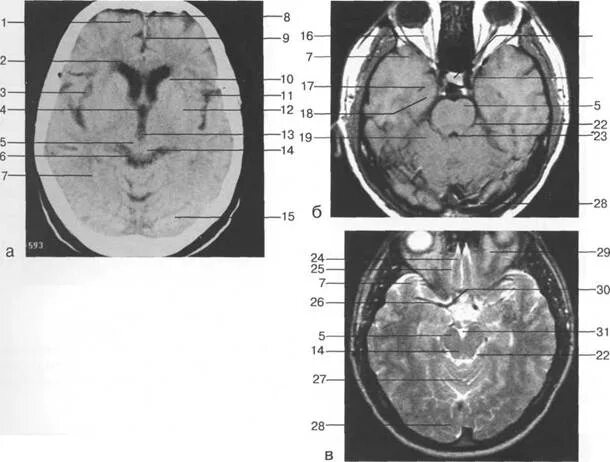

Цистерны на кт